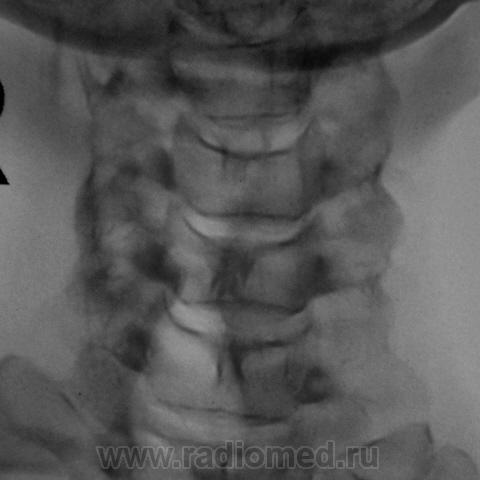

Я в протоколе, отметил нарушение статической функции в виде формирования патологического кифоза, отметил антелистез С2, С3, а также указал, что "это" свидетельствует о нестабильности в сегментах С2-С3, С3-С4.

У данной пациентки - выраженное нарушение статики, а значит смело можно писать дискоз + снижение высоты межпоз. диска в С5-С6 позв. сегменте = остеохондроз.

1.Касаемо остеохондроза С5-6 - вне всякого сомнения и...не вчерашний.

3. Касаемо нестабильности в в\шейном отделе, мне кажется - надумано, тем более, что хотим мы или не хотим, целый ряд специалистов указывают на допустимую нормальную подвижность в пределах 0,3 см максимум.

4. Касаемо ретролистеза С6 - вне всякого сомнения, ибо до 0,4 см...если не немного больше.

нарушение статики ШОП в виде кифоза, признаки остеохондроза и ункоартроаза.

2. Кифотическая деформация (она же функциональная установка по Игорю Ивановичу, она же - анталгическая - по Валетнину Львовичу, что, впрочем, одно и то же по сути)-вне всякого сомнения....но она же - предупреждение о клиническом ухудшении; кстати - если придираться, то и кривошея влево, хотть и умеренная, но есть, более чем уверен, что из той же оперы.

5. Поход к мануалисту и наличие кифоза, ретролистеза С6, кривошеи, поворота среднешейного отдела вокруг вертикальной оси, хоть и легкого, но имеющегося, приводят к мысли, что имеет место подвывих в одном из дугоотростчастых суставов в пределах С4-С7....вот только вопрос - какого...вот он то и привел к обострению клинической ситуации с остеохондрозом....не вчерашним....